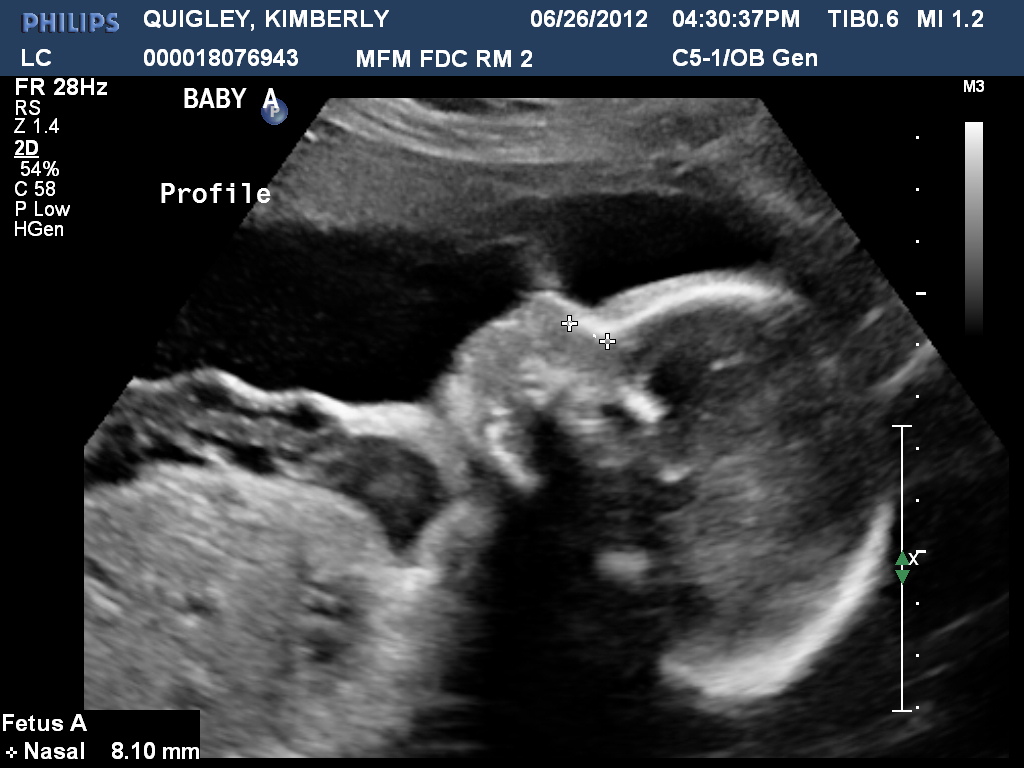

As you can read, Allison's profile image:

As you can read, Emily's profile image: